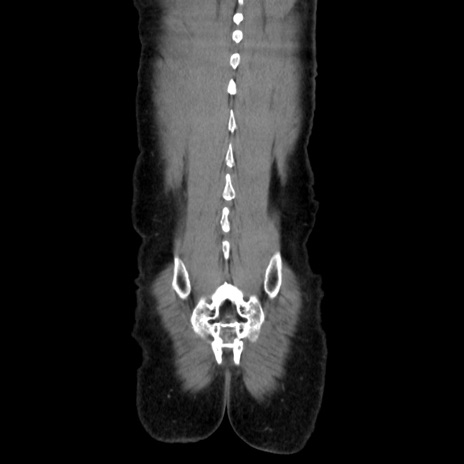

症例37(冠状断像)

【症例】40歳代 男性

【主訴】腹痛

【現病歴】4時間ほど前に電車に乗車中に臍部上より腹痛出現。徐々に増悪し起立困難となり、救急外来受診。生ものは数日食べていない。今朝お雑煮を食べた。

【身体所見】BT 36.8℃、BP 117/84mmHg、HR 91/min、SpO2 97%、苦悶様、腹部:臍上部広範囲圧痛あり、反跳痛±

【データ】WBC 8100、CRP 0.03